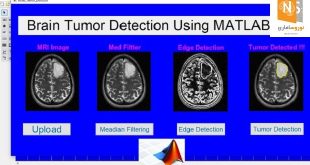

مغز از تداعی “خویشتن” با “مرگ” اجتناب می کند

به گزارش نوروسافاری به نقل از روزنامه ی گاردین، دور زیدرمن و همکارانش برای پی بردن به این که مغز چگونه افکار مربوط به مرگ را مدیریت می کند آزمونی را طراحی کردند که با تولید سیگنال های تعجب در مغز سر و کار داشت. آن ها از داوطلبان خواستند در حالی که فعالیت مغزی شان زیر نظر بود به چهره هایی که به صورت ناگهانی بر روی صفحه نمایش ظاهر می شد نگاه کنند. چندین مرتبه چهره ی خود شخص یا چهره ی یک فرد غریبه روی صفحه ظاهر می شد که در پی آن ها چهره های متفاوتی نیز می آمد. با مشاهده ی چهره ی نهایی، مغز بر اثر تعجب چشمک می زد. چرا که تصویر با آنچه در ذهن آزمودنی پیش بینی شده بود ناهمساز بود.

بالای چهره های ظاهر شده بر صفحه ی نمایش کلمات متفاوتی نمایان می شد. نیمی از موارد کلمات مرتبط با مرگ بودند مثل “مجلس ترحیم” و “به خاک سپاری”. دانشمندان دریافتند اگر چهره ی خود شخص در مجاورت کلمات مرتبط با مرگ ظاهر می شد مغز آنها سیستم پیش بینی اش را خاموش می کرد و از پیوند دادن “خویشتن” با مرگ سر باز می زد و هیچ سیگنال تعجبی ضبط نمی شد.